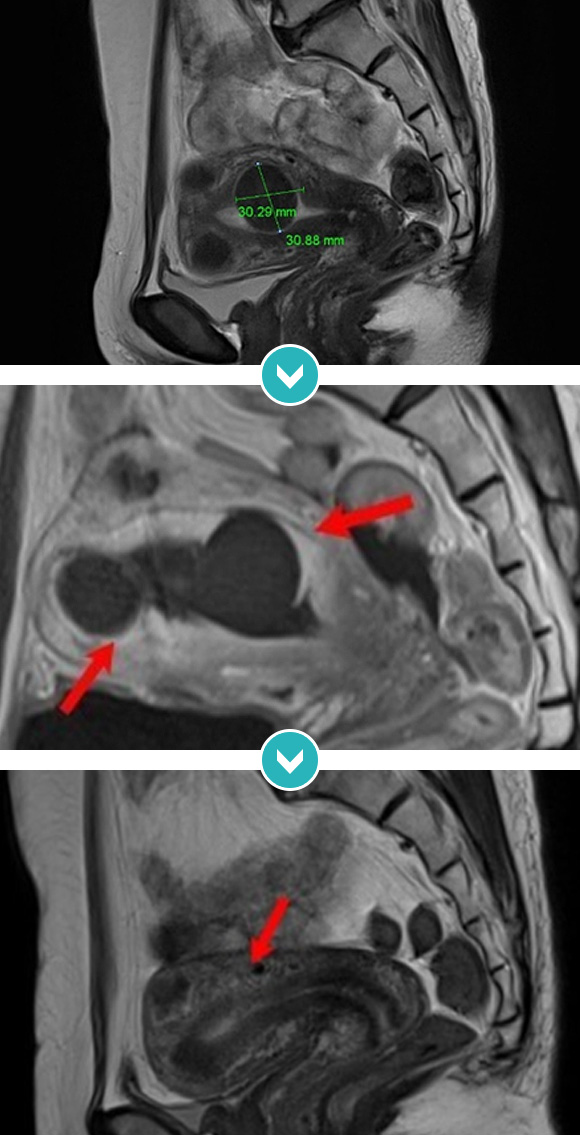

7cm 자궁근종 하이푸 치료 후 90%이상 괴사, 8개월 추적관찰